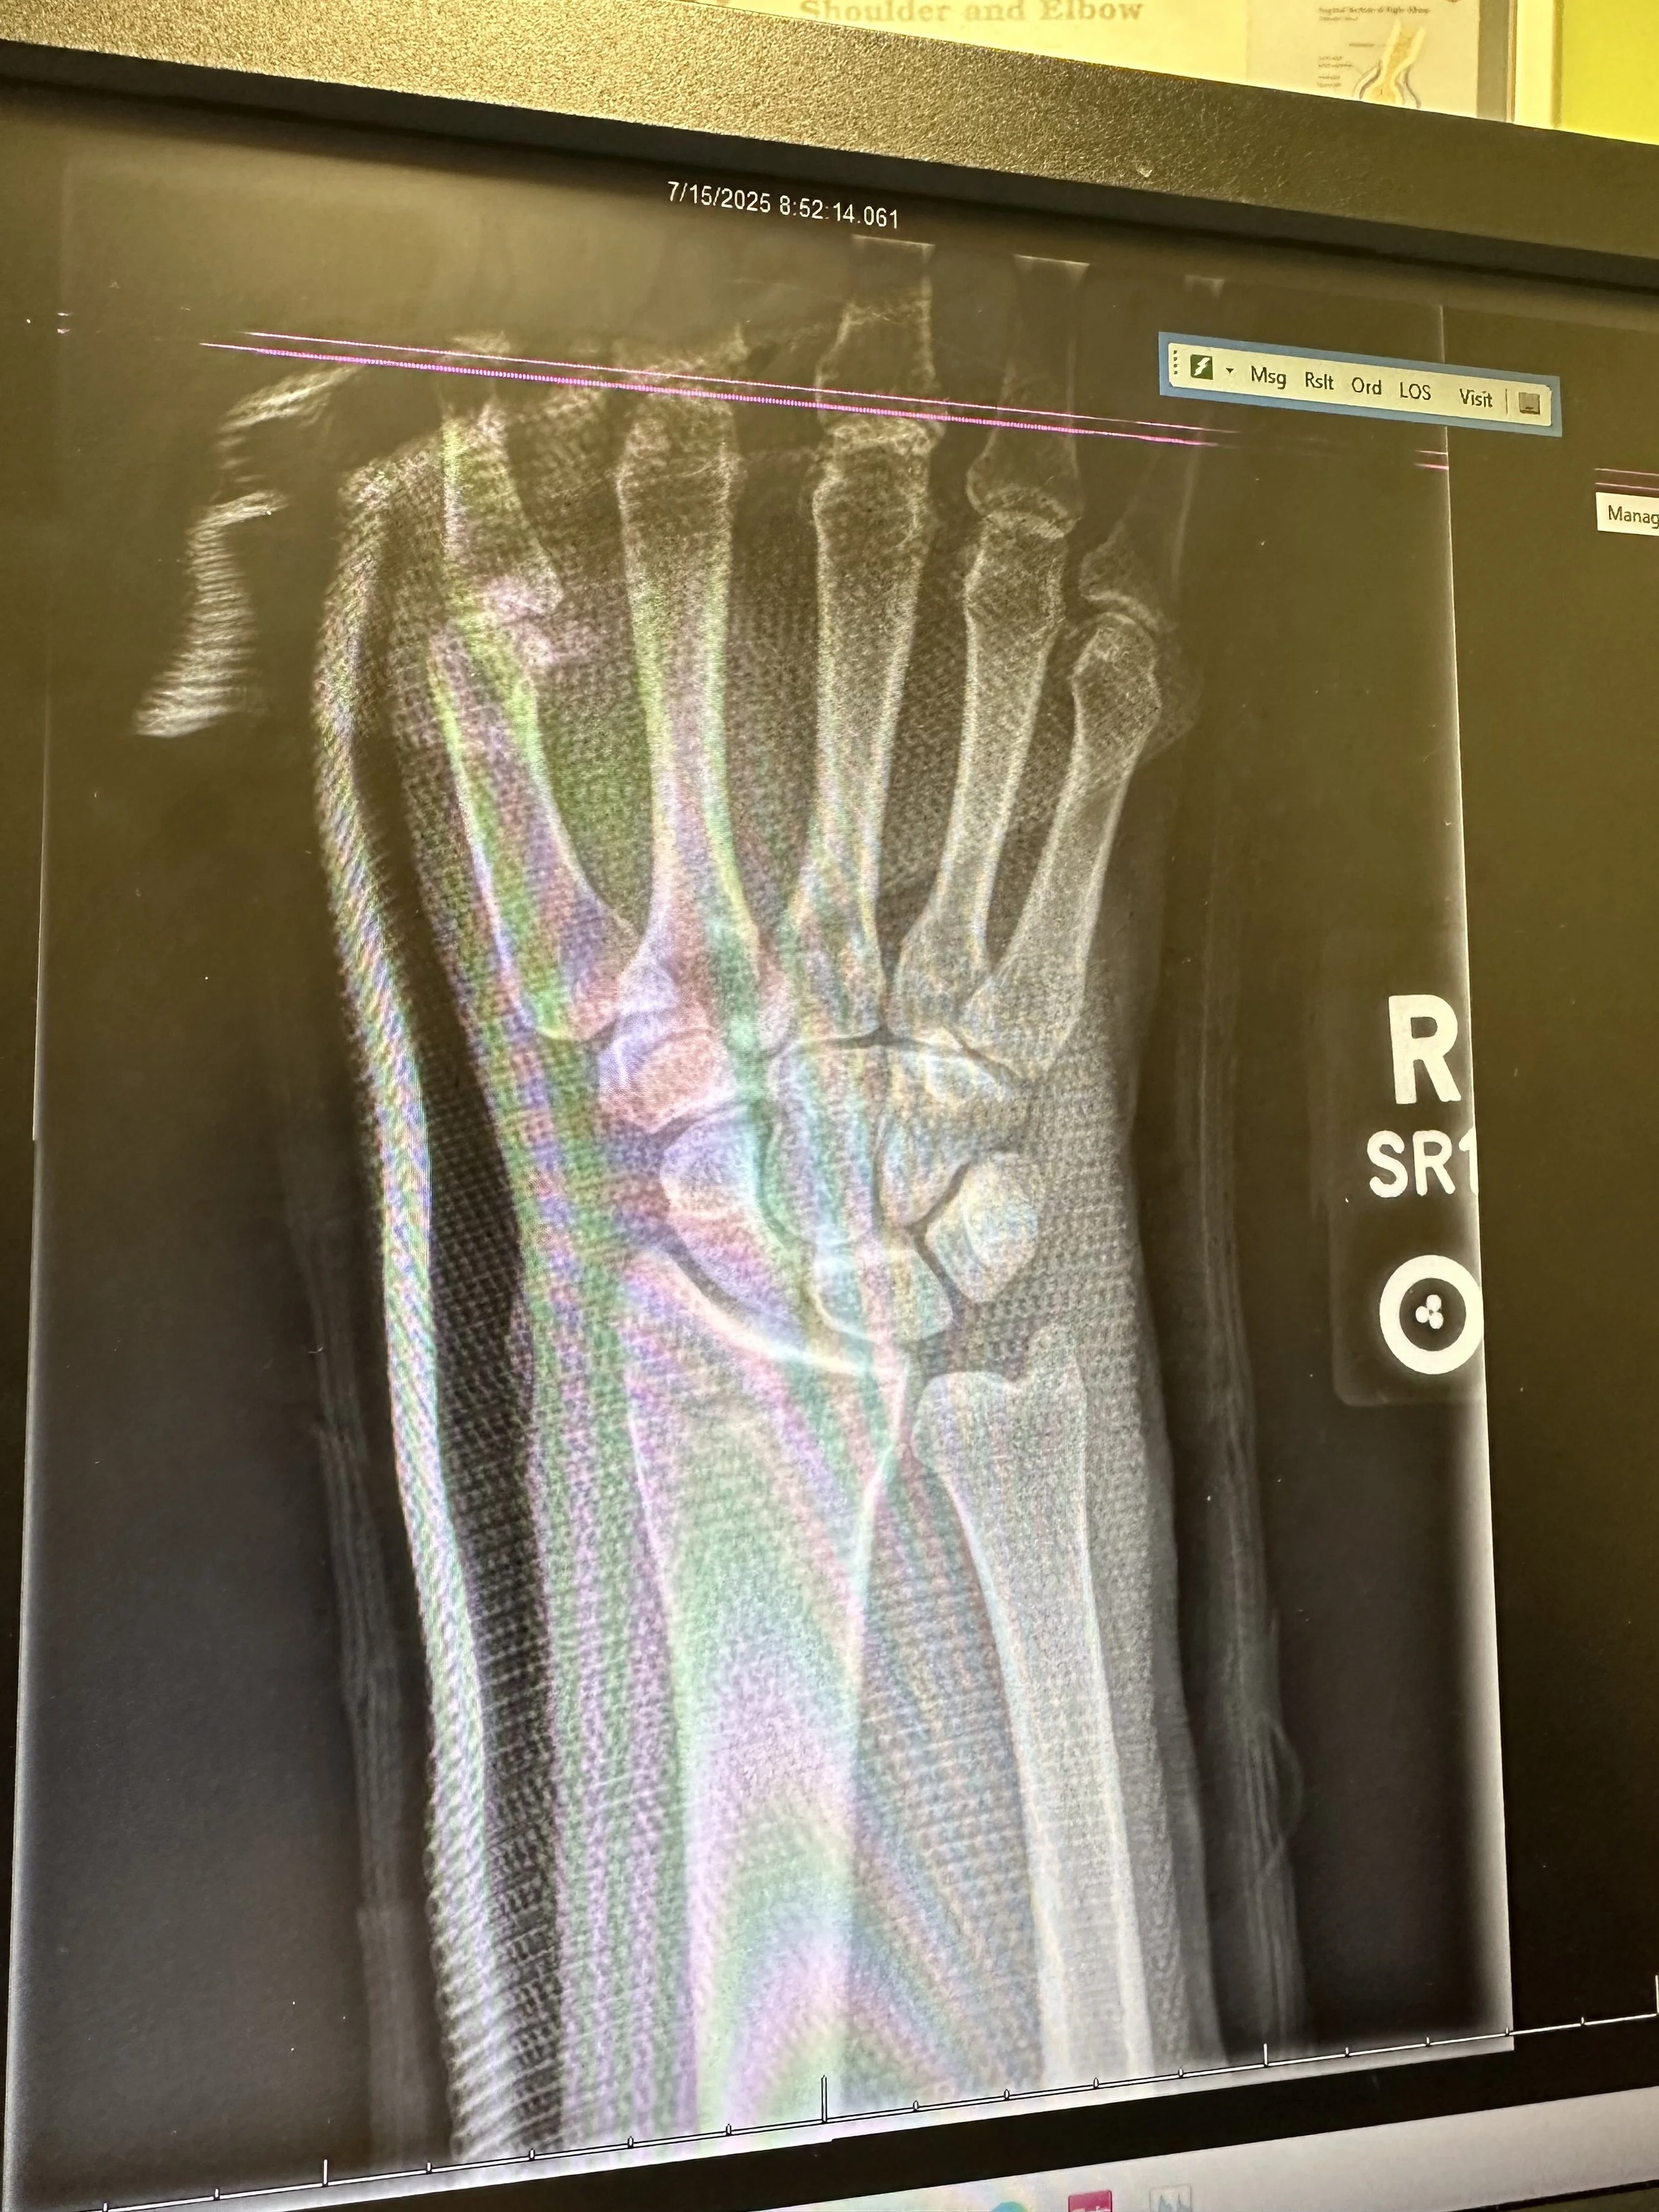

Medical X-ray of a right wrist showing bones and joints.

On July 12, 2025, I was involved in a serious motorcycle accident that left me with a fracture, multiple torn ligaments, and bone contusions, that will have to undergo surgery. Thankfully, I'm on the road to recovery, but it's going to be a long and challenging journey.